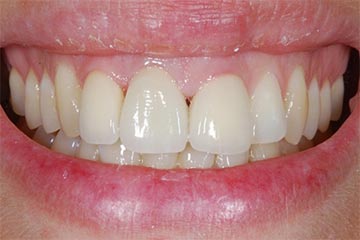

Faccette estetiche in ceramica